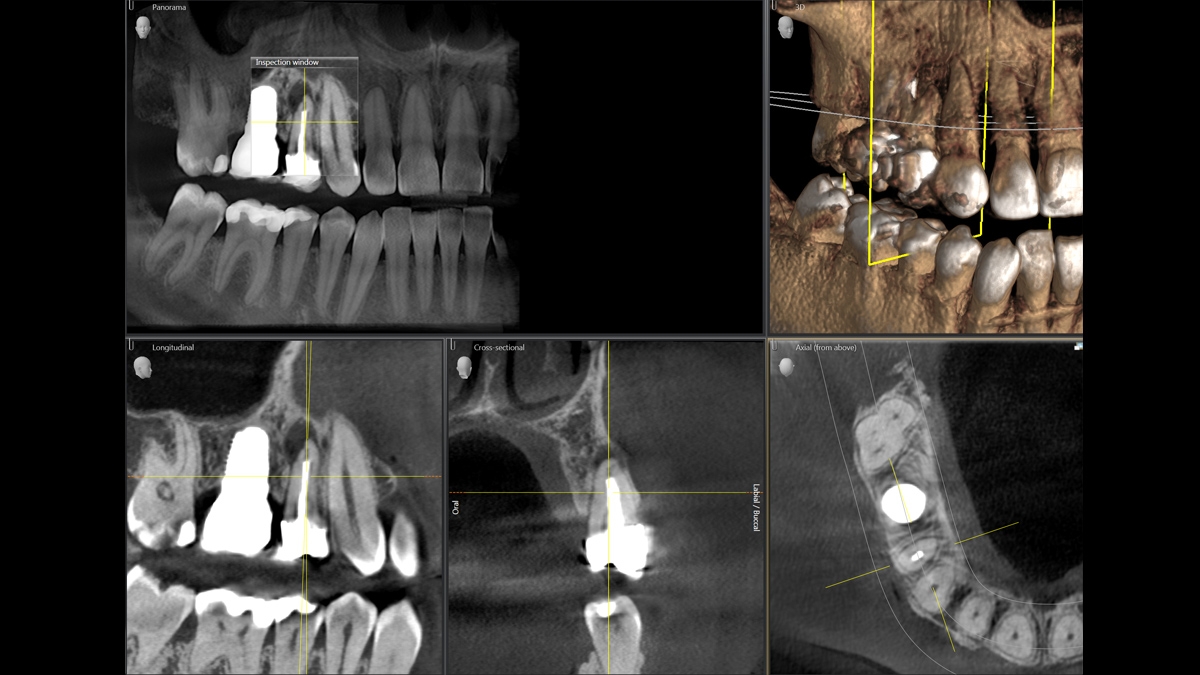

We developed a 10-point concept for easy patient positioning and X-ray imaging. Our concept is primarily about two things: high image quality and comfort for the patient and the assistant. This concept supports and provides the tools needed to ensure high-quality images for treatment analysis and focuses on ergonomics and comfort for the patient and assistant.